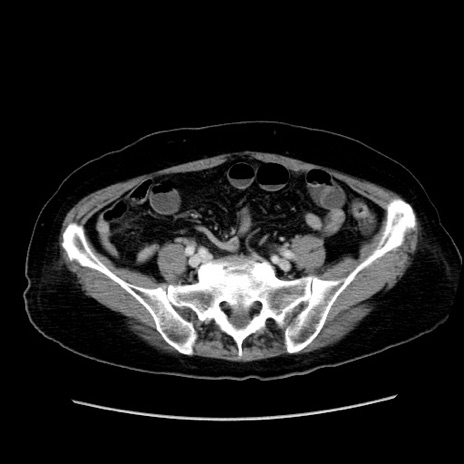

冠状断像

【症例】80歳代女性

【主訴】下腹部痛

【現病歴】約8時間前より下腹部痛の出現あり、救急外来受診。

【既往歴】両側付属器切除

【身体所見】意識清明、下腹部正中に手術痕あり、その部位に一致して圧痛と反跳痛あり。腸蠕動音は亢進。

【データ】WBC 9300、CRP 0.15